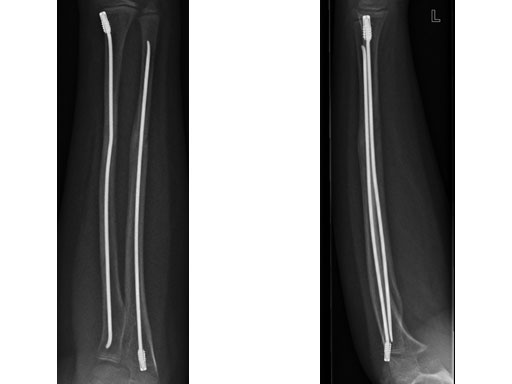

Case 1: Transverse forearm, shaft fracture (22D/4.1), 9-year-old girl.

Case provided by Theddy Slongo, Bern, Switzerland